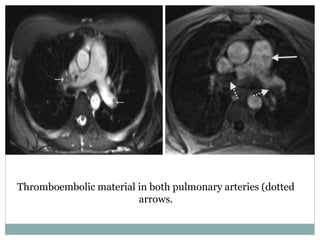

Thromboembolic material in both pulmonary arteries (dotted

arrows.

(a) CT angiography shows thromboembolic material in both lower lobe pulmonary arteries

(arrows). (b) High spatial resolution MR angiography demonstrates the same findings

(arrows).